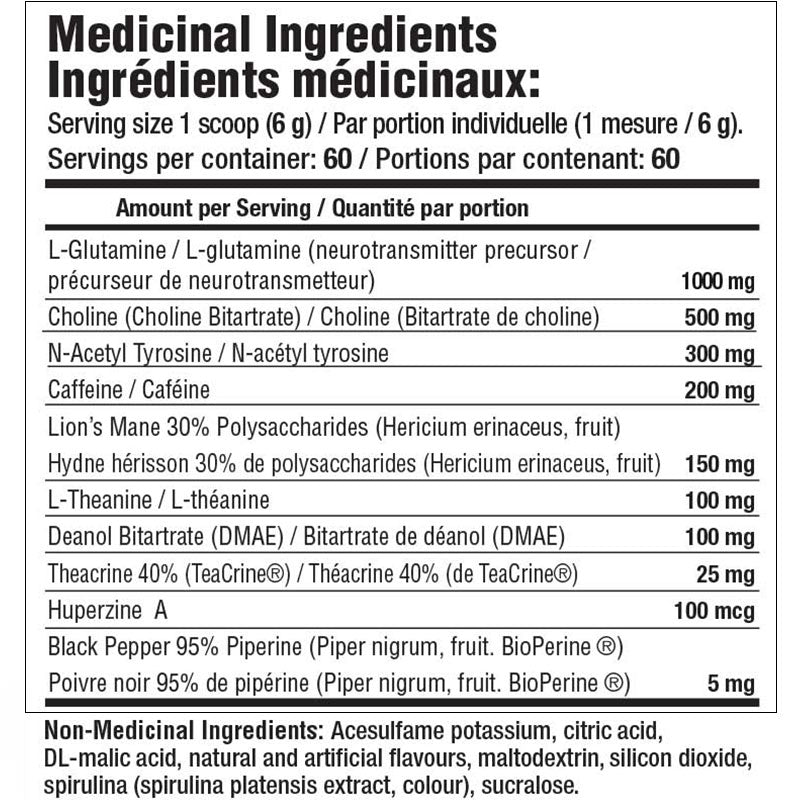

1000 mg | Glutamine

200 mg | Caffeine

500 mg | Choline

100 mg | L-Theanine

300 mg | N-Acetyl tyrosine (NALT)

100 mcg | Huperzine A

100 mg | DMAE (Deanol)

5 mg | Piperine

63 mg | Theacrine

150 mg | Lions Mane